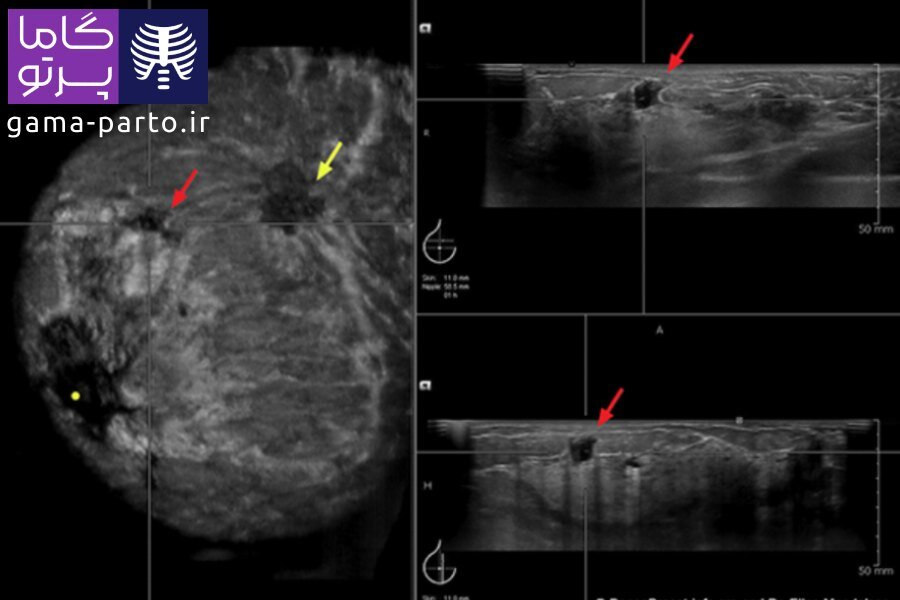

سرطان پستان در سونوگرافی چگونه است؟

در تصاویر سونوگرافی سرطان سینه، کیستهای پر از مایع معمولا به شکل دایرهها یا بیضیهای کاملا سیاه دیده میشوند. این در حالی است که تودههای سرطانی در مقایسه با کیستها معمولا کمی روشنتر و با لبههای نامنظم دیده میشوند.

تودههای مشکوک ممکن است دارای شکل نامنظم، حاشیههای نامشخص یا رشد در جهات مختلف باشند. با این حال، تشخیص سرطان پستان تنها بر اساس سونوگرافی سینه ممکن نیست.

بسیاری از تودههای غیرطبیعی ممکن است خوشخیم باشند. پزشک متخصص بر اساس شکل، تراکم و سایر ویژگیهای تصویری تودهها تصمیم میگیرد که آیا به آزمایشهای تکمیلی مانند بیوپسی یا ماموگرافی نیاز است یا خیر.